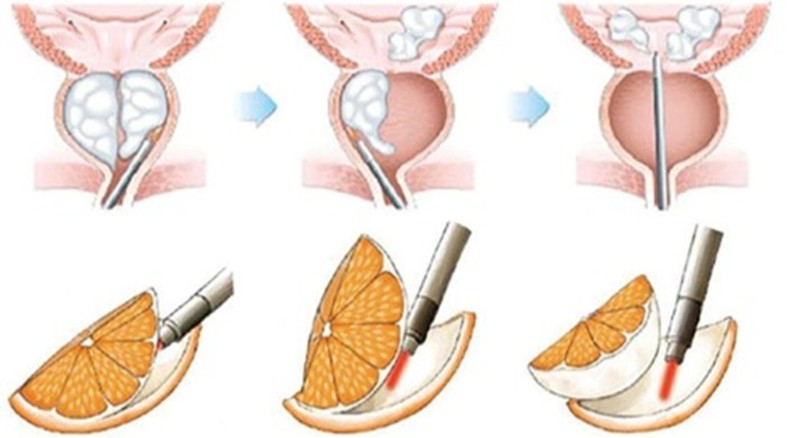

Intervenția care vă este propusă se numește enuclearea endoscopică a prostatei. Ea este practicată cu ajutorul unei fibre si a unui laser. Acest tratament este realizat fără nici o incizie, ci doar pe căile naturale urinare (transuretral). Intervenția constă în lărgirea canalului uretrei prin rezecția adenomului ce se găsește în centrul prostatei. Zona periferică a prostatei este prezervată.

Această intervenție este realizată sub anestezie generală sau rahidiană. Medicul urolog introduce la nivelul canalului uretral un aparat numit endoscop care îi permite vizualizarea uretrei si reperarea prostatei. Cu ajutorul unei fibre laser medicul urolog poate introduce endoscopul între adenomul de prostată și capsula prostatei. Astfel, făcând tot turul adenomului de prostată, medicul urolog detașează adenomul de capsula prostatei și împinge adenomul în vezica urinară. Adenomul complet liber este extras cu ajutorul unui instrument ce se numește morcelator, care permite morcelarea (tăierea) adenomului de prostată în mici fragmente ce pot fi extrase prin aspirare prin interiorul endoscopului.

Fragmentele de prostată extrase sunt trimise pentru a fi analizate histopatologic. O sondă uretro-vezicală cu trei căi este montată la finalul intervenției.